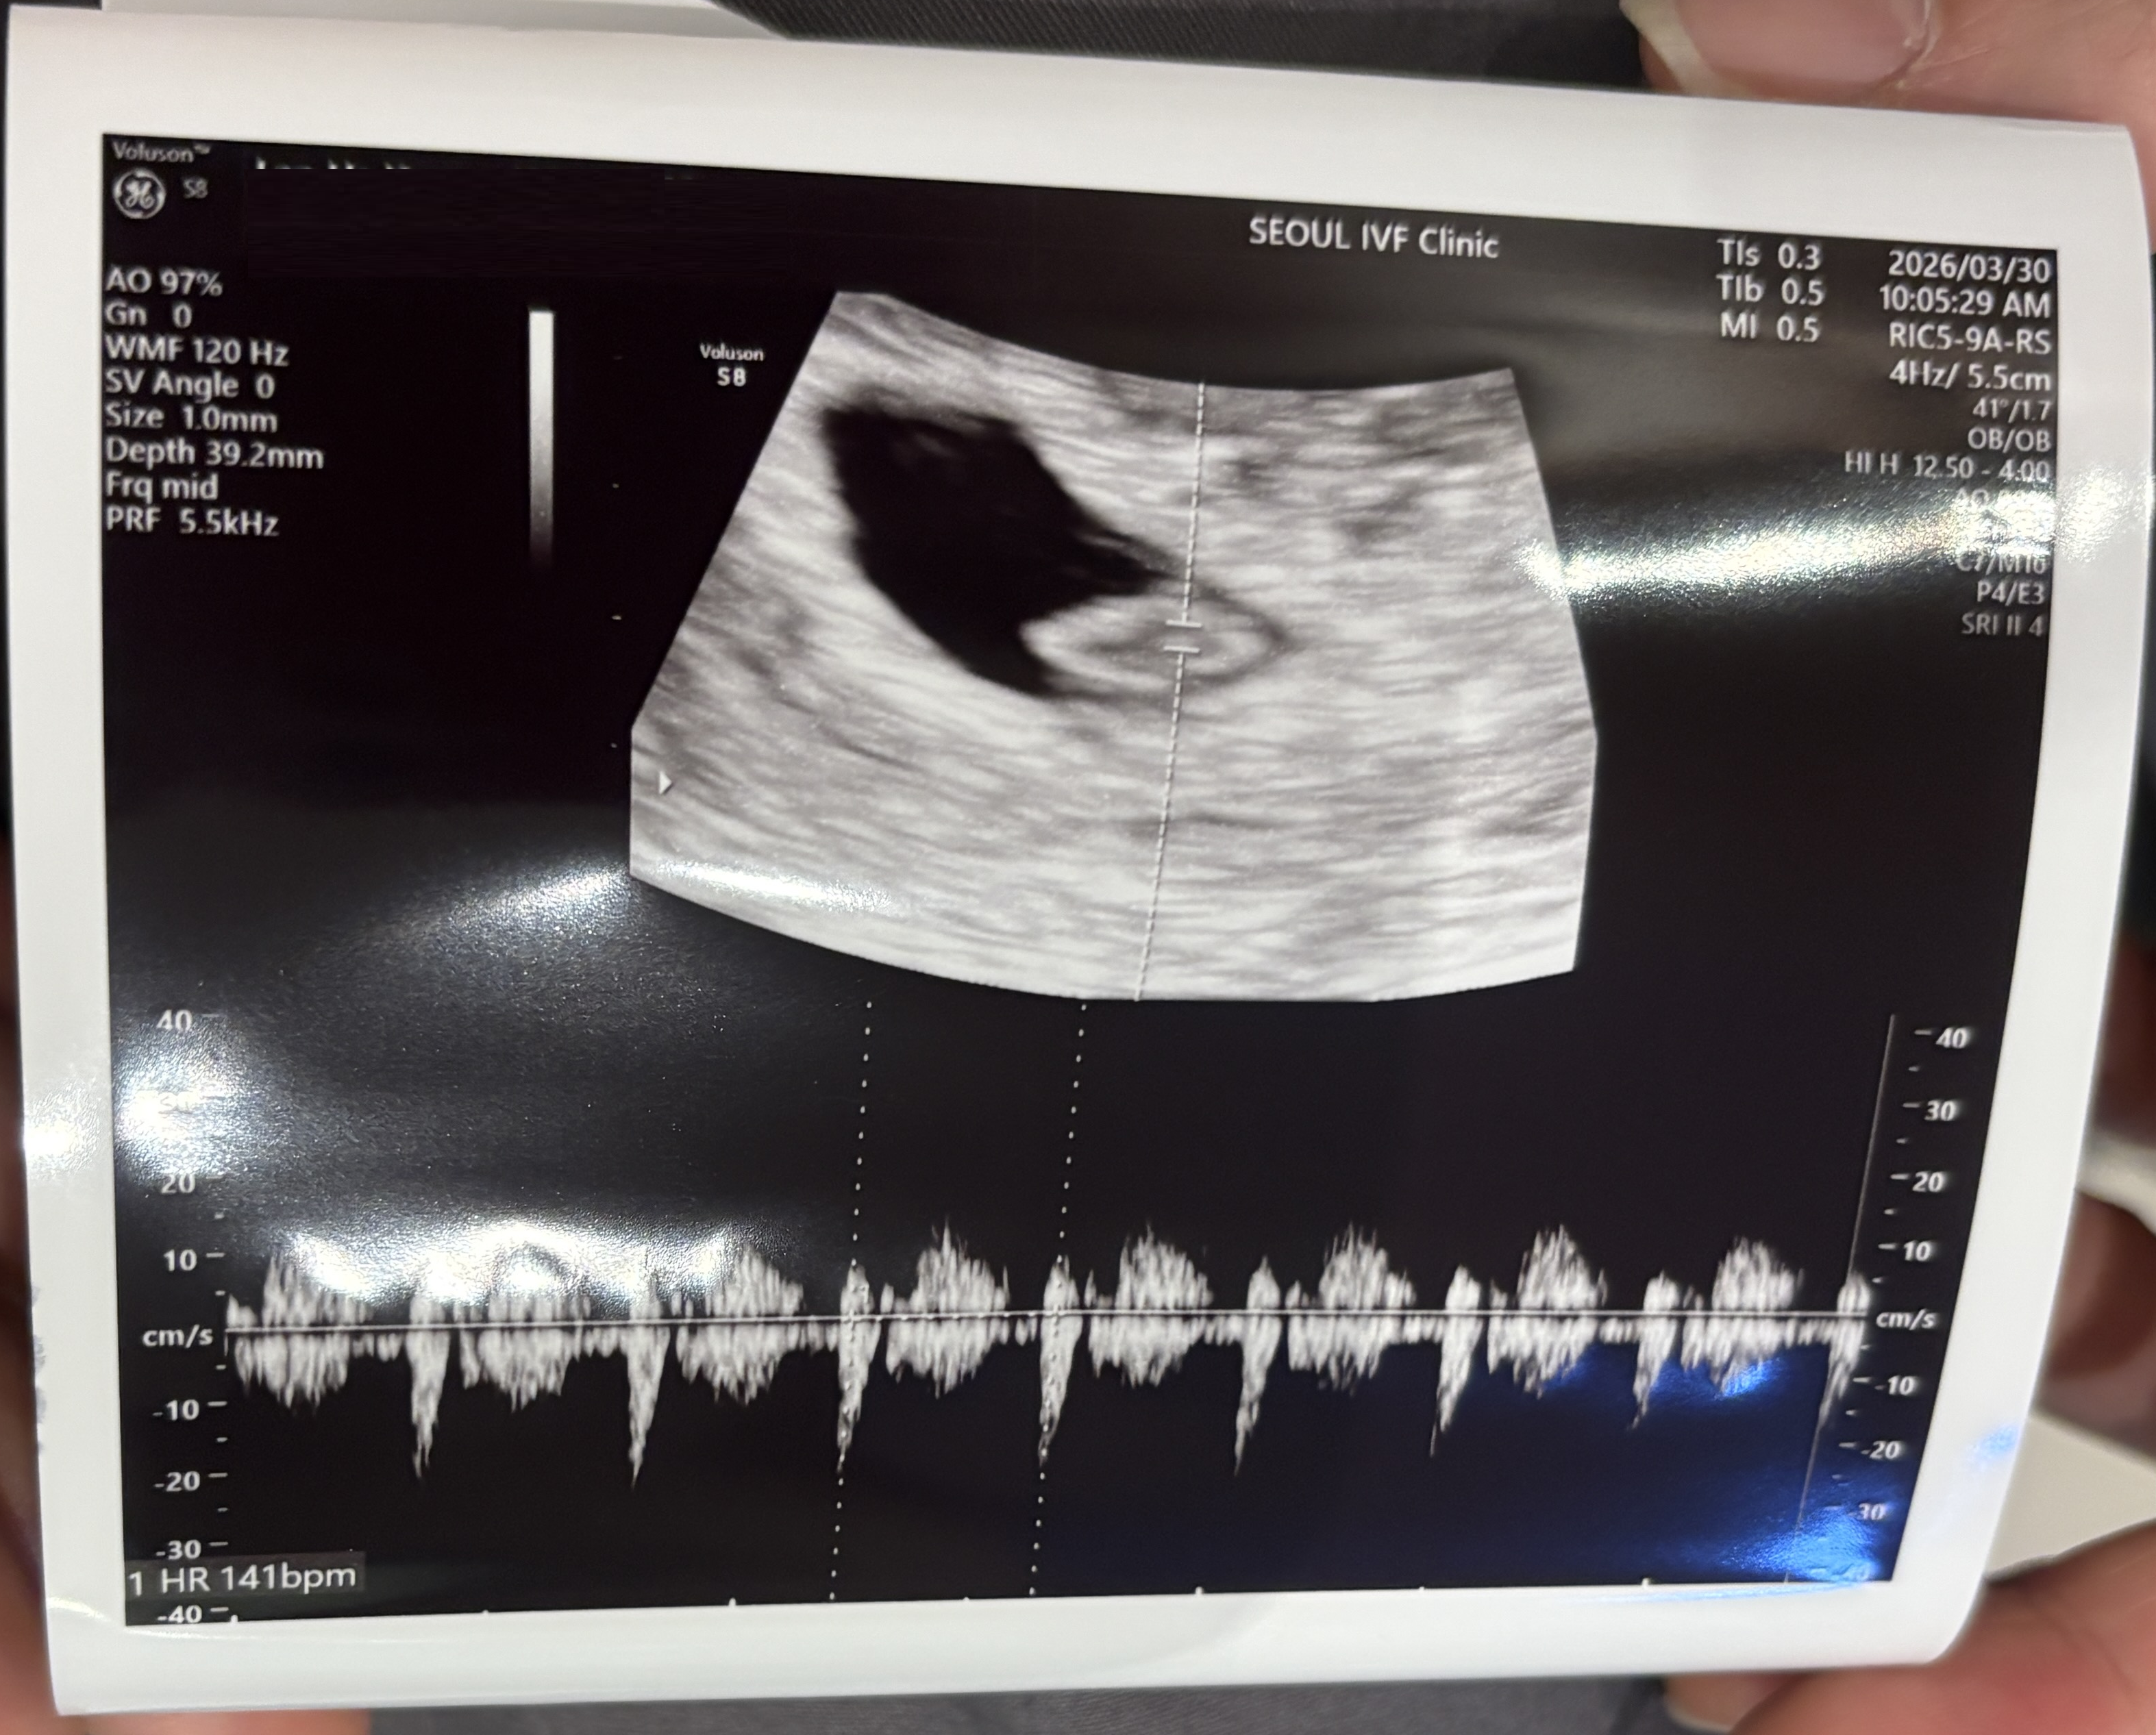

| 가슴 떨리는 임신 이야기를 공유해 주세요. | 이경훈 원장 덕분에 한 번의 시도로 임신에 성공하게 되었습니다. 초음파를 통해 아기의 심장 소리를 확인했을 때 정말 큰 감동을 느꼈습니다. |

| 치료 도중 느꼈던 가장 기뻤던 순간과 절망적인 것들은 무엇인가요? 잊지 못할 경험이 있나요? | 임신융모막호르몬 수치가 잘 더블링되었을 때와 남편과 함께 좋은 소식을 나누었던 순간이 가장 기뻤던 기억입니다. 절망적으로 느꼈던 순간은 따로 없었습니다. |